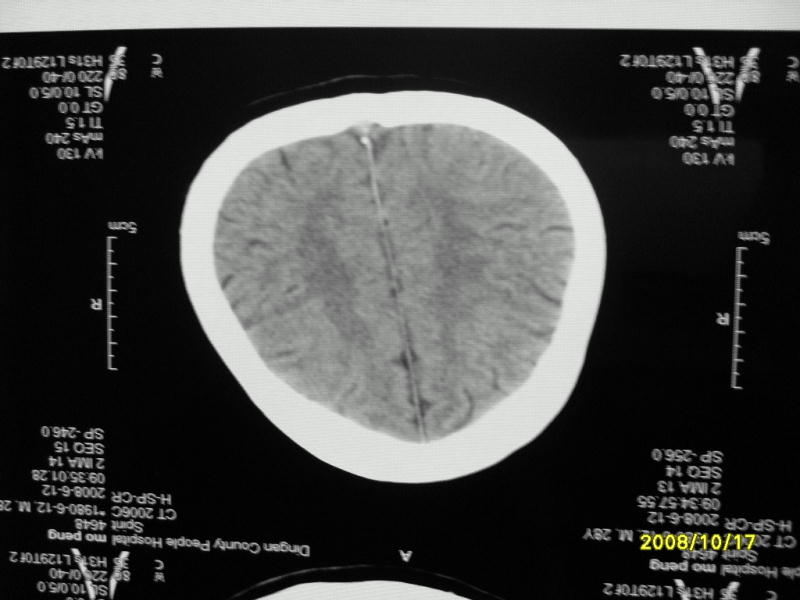

检查名称:     ct颅脑平扫           男     28岁

表现:左顶叶见斑点状致密影。边缘清,大小约0。3*1。0cm,余脑实质密度及灰白质结构示见异常。脑室系统大小,形态,密度未见异常。脑沟。脑裂。脑池未见异常密度影。中线结构无移位。

印象:左顶叶少许钙化灶

左顶叶见斑点状致密影。边缘清,大小约0。3*1。0cm,余脑实质密度及灰白质结构示见异常。脑室系统大小,形态,密度未见异常。脑沟。脑裂。脑池未见异常密度影。中线结构无移位。

印象:左顶叶少许钙化灶。